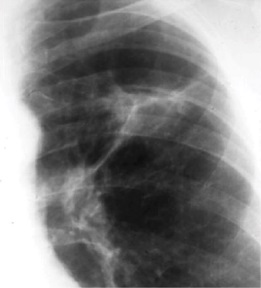

4. The primary lesion is known as the Ghon focus. Draining lymph nodes can also become infected. The initial Ghon focus and newly infected lymph nodes are known as the Ghon complex.

5. The infection can stop here and remain contained for years within the granuloma. This is known as latent tuberculosis. Individuals are not infectious in this time and are also asymptomatic. Over time, the granulomas can heal, and will undergo calcification and fibrosis, thus appearing on a chest X-ray. This calcified Ghon complex is known as a Ranke complex.

Ghon Complex on Chest X-ray